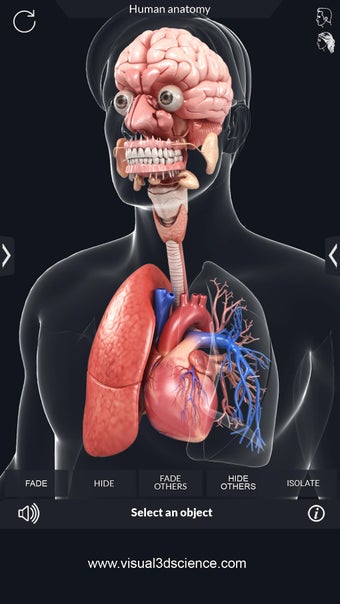

My Organs Anatomy es una aplicación de anatomía 3D gratuita desarrollada por Visual 3D Science para usuarios de Android. Esta aplicación proporciona un modelo 3D altamente realista de los órganos humanos que se puede girar 360°, acercar y alejar, y ver desde cualquier ángulo. La aplicación está diseñada para proporcionar una mirada detallada a la anatomía de los órganos humanos y ofrece varias características para ayudar a los usuarios a explorar y aprender.

La interfaz fácil de usar de My Organs Anatomy permite una navegación sencilla, lo que facilita la selección, rayos X, ocultación y visualización de órganos individuales. La aplicación también incluye un modo de animación, opciones de búsqueda y un panel de información que proporciona información relacionada. Además, la aplicación ofrece pronunciación de audio para todos los términos anatómicos, e incluso los usuarios pueden dibujar o escribir en la pantalla y compartir capturas de pantalla.